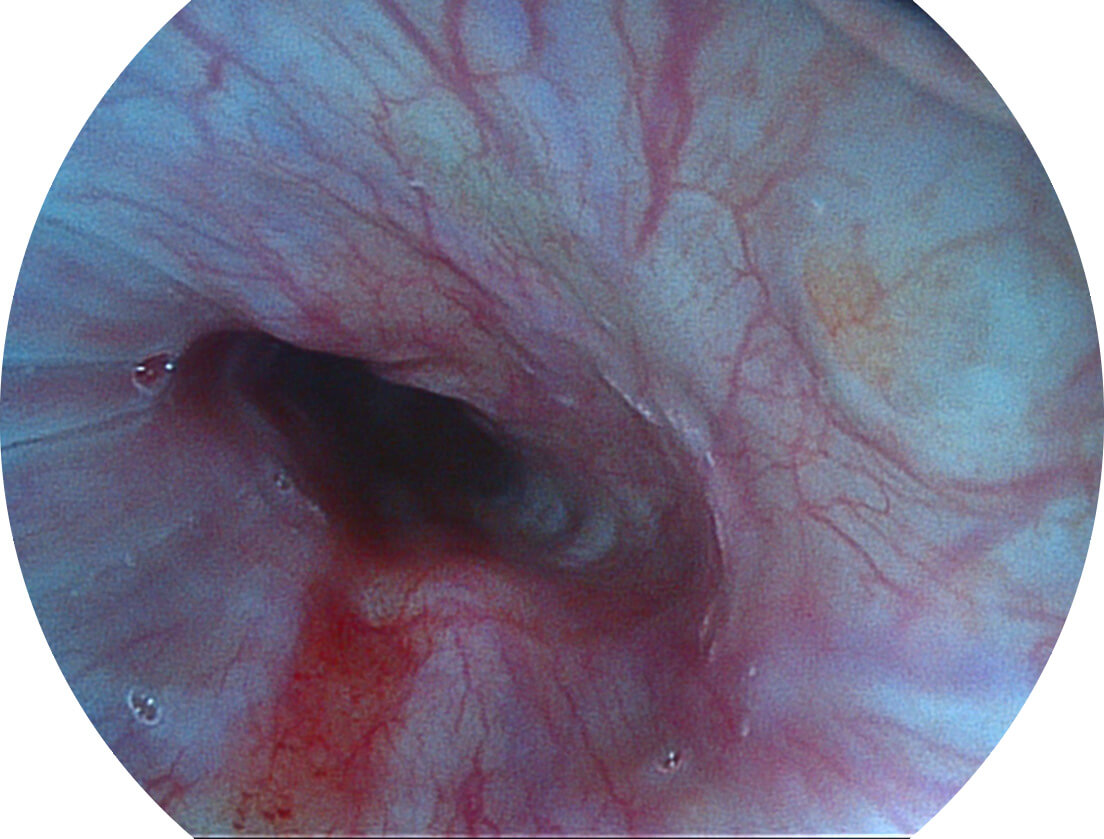

白光图像

SFI图像

Spectral Focused lmaging, SFI

图像具有高亮度、高黏膜血管颜色对比度的特点,且不改变粘液、食物残渣、粪便的基本颜色,可在中远景下进行观察,助力消化道早期疾病的诊断。